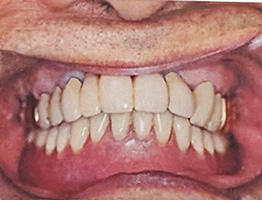

30年経過症例 / 92歳(2025年現在)・男性

1995年 上顎インプラント埋入時(61歳)

2002年 下顎インプラント埋入時(69歳)

92歳(2025年現在):シッカリ噛める事で咀嚼筋・表情筋が鍛えられ顔に張りがあり高齢にも拘らず縦ジワが全く見られません。最近まで車の運転をされていました。